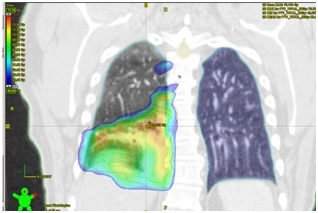

Рекомендована химиолучевая терапия: на основной процесс в правом легком, лимфоузлы средостения до СОД 66Гр за 33 фракции на фоне еженедельного введения химиотерапии: Паклитаксел 50 мг/м2 + Карбоплатин 2 AUC.

18.01.2017 – 03.03.2017. Радикальный курс лучевой терапии на первичный очаг в правом легком и зоны регионарного лимфоотока (ПЭТ – позитивные лимфоузлы средостения) в разовой дозе 2Гр до суммарной дозы 66 Гр за 33 фракции. Продолжительность лечения 6 недель. Выполнено 6 введений Паклитаксел 50 мг/м2 + Карбоплатин 2 AUC еженедельно.